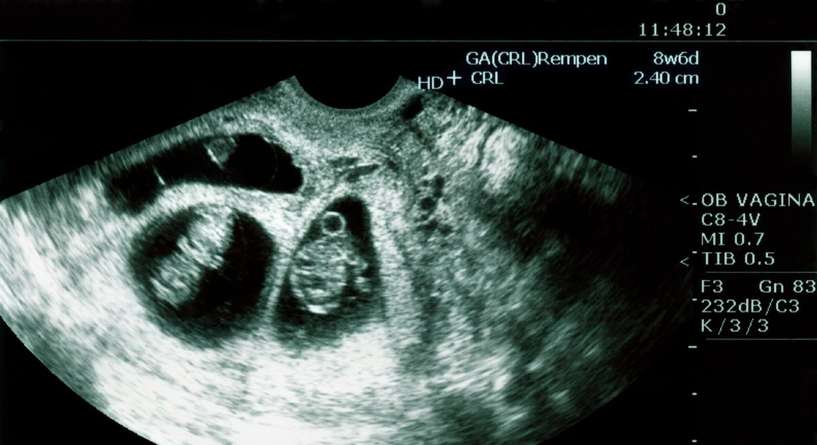

اليك اخطاء السونار في التوأم والبنت والولد تابعينا لتتعرفي اكثر الى احتمالات وقوع الاخطاء في تحديد الجنسين والتوام ومتى يكون الوقت مثاليا لاجراء السونار!

عرفناك في ما سبق على قراءة اختصارات السونار للحامل لكن هل يخطئ السونار؟ يعتمد الأطباء على السونار لمعرفة نوع الجنين والتاكد من الحمل بتوام ومنذ لحظات الحمل الأولى يرغب الاهل بمعرفة هذه المعلومات بواسطة اكثر الوسائل شيوعا لذلك الا وهي السونار. ولن أحيانا تحدث أخطاء كثيرة خاصة في امر البنت وتخيب امال الاهل بعد ان تحضروا نفسيا لهذه الهدية. تابعينا لتتعرفي اكثر على الأخطاء الممكن حدوثها في السونار.

تعتمد النساء بالعادة ومنذ الازل على تكهنات كبار السن وذوي المعرفة للتاكد من جنس الجنين ومع التطور اصبحت هناك طرق لتحديد الجنس الذكر او النثى ومن أهمها السونار او ما يسمى بالتصوير بالموجات فوق الصوتية. ويرتكز هذا النوع من التحري على اطلاق موجات فوق صوتية تلامس الجنين في الرحم ثم يعالجها الحاسوب ناقلا بذلك صورة الجنين ليتمكن الطبيب من تفرقة البنت عن الولد.

ولكن تقع بعض الأخطاء في هذا السياق خاصة في سونار البنت وذلك بسبب التسرع في الخضوع للسونار اذ ان التوقيت المثالي للقيام به يتراوح ما بين نهاية الشهر الثالث من الحمل الى نصف الشهر الرابع وسيكون من الأفضل التاخر اكثر. والعلامة الأولى على ان الجنين ذكر هي عضوه الذكري الذي يتضح مع مرور شهور الحمل.

ان الحمل بتوام من اجمل التجارب التي قد يمر بها الاهل وعندما تكتشف الام انها حامل بتوام لا تنسى المشاعر التي تنتابها ما دامت على قيد الحياة خاصة عند الكشف عن نوع جنس التوام الذي يحتاج لمعاملة خاصة اثاء القيام بالسونار. فتطلب الطبيبة من المراة الحامل ان تغير وضعيتها لتتمكن من تصوير البطن من زوايا شتة واضحة وتدوم الجلسات لوقت أطول.

لكن أحيانا يقع الخطا عند القيام بالسونار للتوام بسبب التصاق الجنينين ببعضهما البعض او بفعل تصويرهما من زاوية تجعل اكتشاف تعددهما صعبا وذلك عندما يتم التسرع في القيام بالفحص ومن الأفضل الاختيار الشهر السادس للحامل لذلك لمنع حدوث خطا.